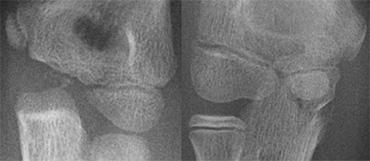

Two cases of overprojection of the capitellum on humeral epiphysis simulating a fracture. Notice olecranon fracture on the right

Gãy lồi cầu ngoài (6).

Hình ảnh lồi cầu xương cánh tay nhô ra quá mức trên phần hành xương cánh tay có thể giả dạng gãy lồi cầu ngoài (hình).

Gãy lồi cầu ngoài (7).

Bên trái là một vài ví dụ về gãy lồi cầu ngoài.